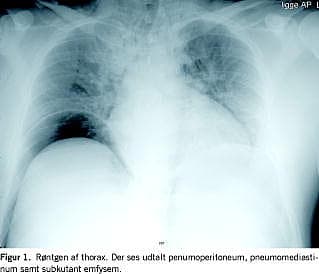

En 28-årig tidligere rask mand blev indbragt akut til skadestuen med pludseligt opståede kraftige mavesmerter. Patienten kunne oplyse, at han kort forinden havde overværet et fysikshow til en privat fest. I ebrieret tilstand ville han eftergøre effekten med peroralt indtag af LN2 , ikke med få ml, men med ca. 15 ml LN2 som han nedsvælgede. Objektivt var patienten akut påvirket og forpint, puls = 120, blodtryk 160/80, oxygensaturation 96%. Abdomen var voldsomt opdrevet og med diffus peritoneal reaktion. Endvidere var der subkutant emfysem fra hals til scrotum. Oversigt over abdomen viste store mængder fri luft intraperitonealt og røntgen af thorax viste såvel subkutant som mediastinalt emfysem (Figur 1 ).